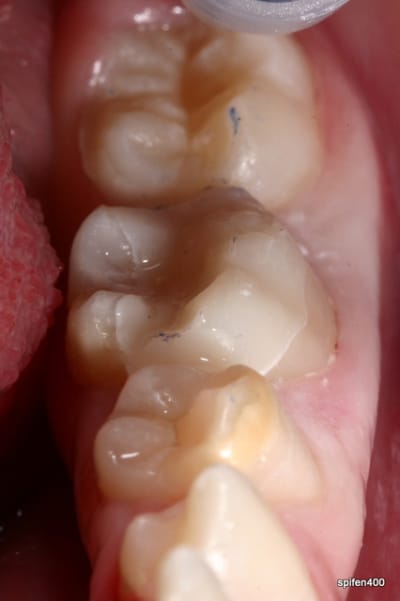

31/10/2011 à 18h09

tiens je me suis chronométré :)

28min :) lol

bon celui la etait un peu long, car provisoire collé au cvi cause durée avec le provisoire trop longue....

donc dur a déposer et obligé d'enlever les résidu de cvi aux US...

ceux qui font pas d'onlay vous proposez quoi là ?

patiente de 13 ans ...

heu spifen 400 c'est pas de la pub lol